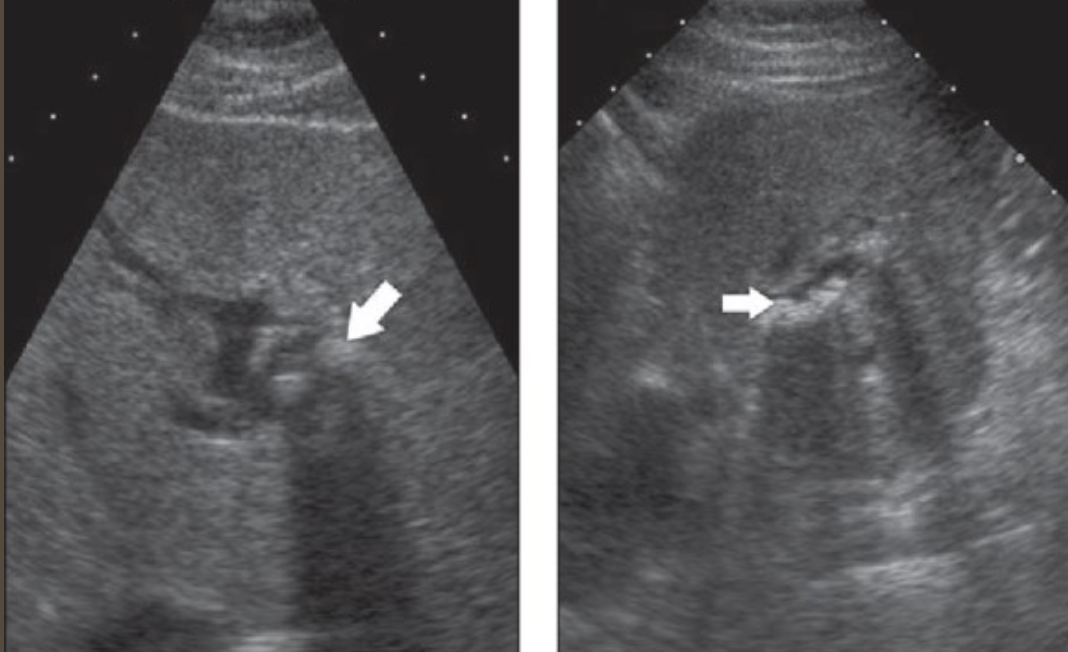

2D US presentation: thin echogenic linear membrane fluttering in lumen creating a true and false lumen

color doppler: fill in both channels → pw shows regular flow in true and weak/no flow in false; asymmetrical kidney perfusion

DDX: AAA (focal dilation, no intimal flap)